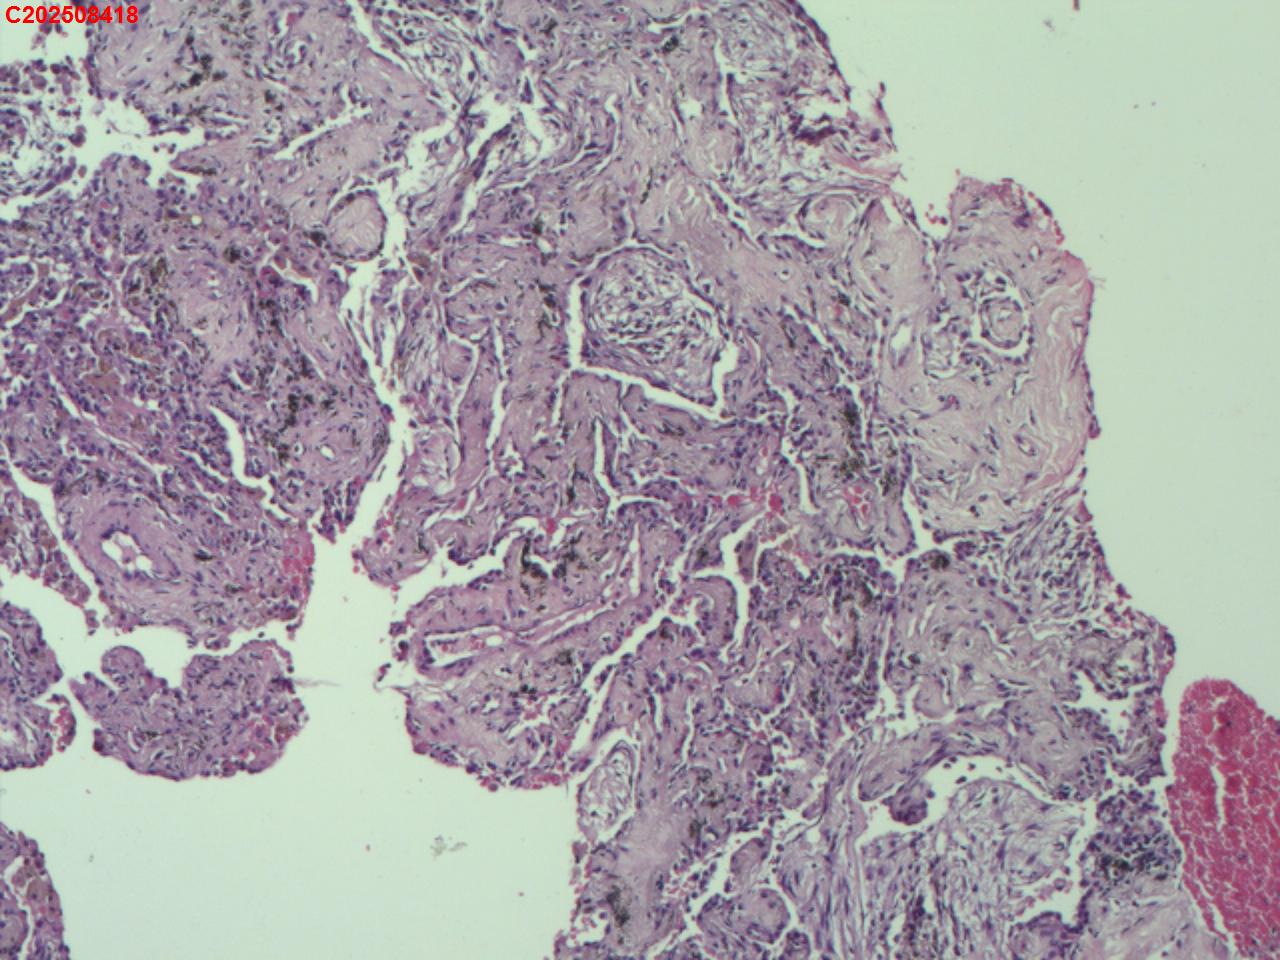

肺穿活检

性别

男

年龄

55岁

临床诊断

肺部感染?结核?占位?

一般病史

胸部(平扫+增强扫描):右肺上叶不均匀强化区,考虑1.结核伴纤维组织增生、炎性细胞浸润,2.占位性病变,请结合临床建议结合病理学检查。右肺上叶多形性病变,结核不除外。考虑为双肺细支气管炎;右肺下叶局限性间质性改变可能,坠积性肺炎不除外。左肺下叶条索影。右侧胸膜局部肥厚、粘连。

标本名称

右肺上叶 穿刺组织

大体所见

肺穿活检5条

图2

首先考虑机化性肺炎。